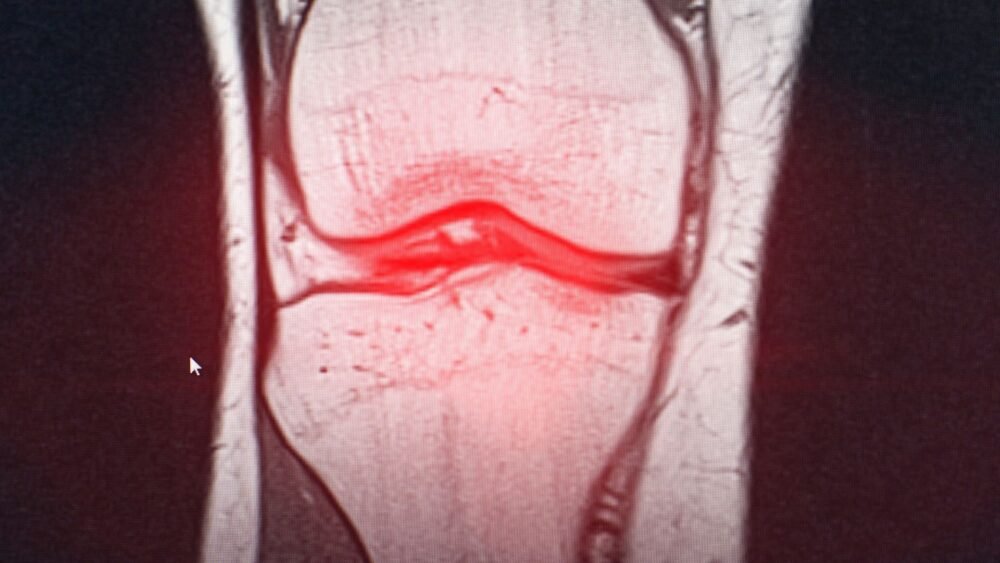

- MRI scan to confirm the tear and assess its severity and location